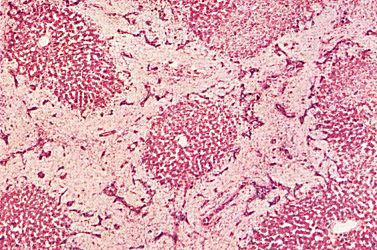

The following slide is of a cross section of the liver. Pig liver has more pronounced connective tissue septae and is used here to demonstrate the septae.

Fig 68-001

Other models to describe a liver lobule are also available.